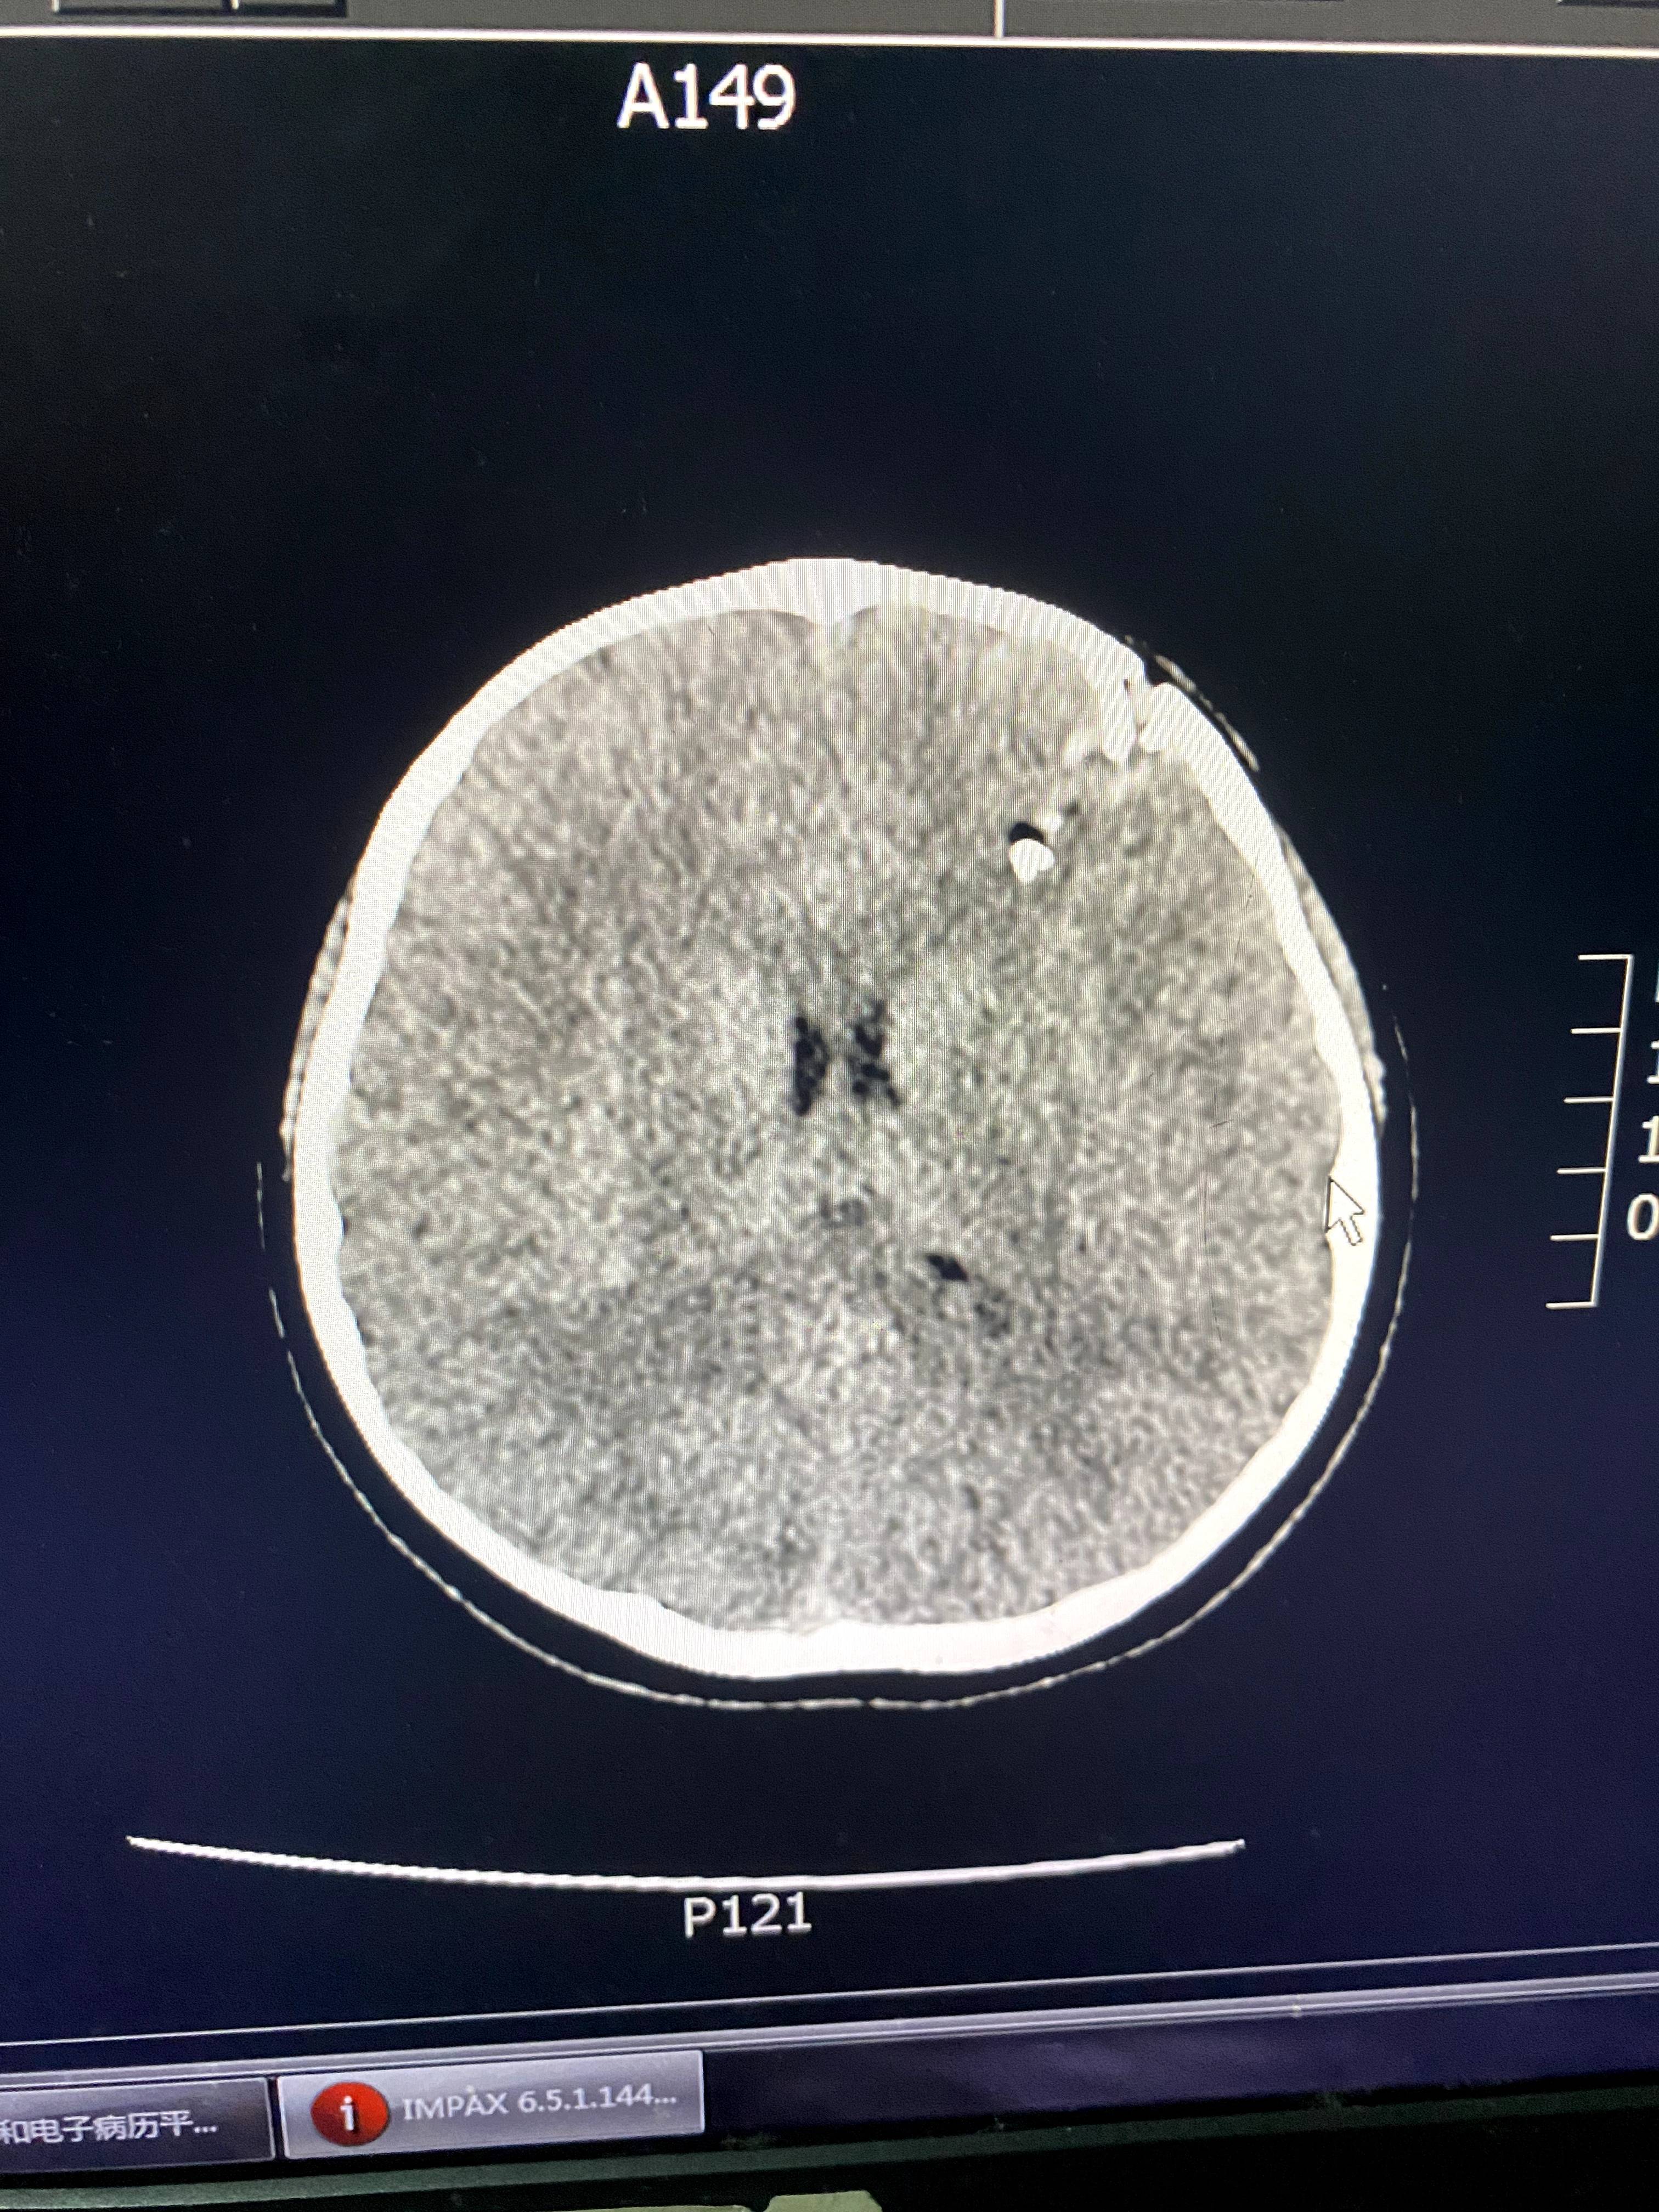

班主任就站在孩子身边。郭洋还没来得及多问,医生就从CT室匆匆赶来,指着电脑上的片子告诉郭洋,“颅骨已经碎了,颅内疑似有异物,要马上做开颅手术。”郭洋说,女儿从小到大几乎没受过什么伤,连感冒都少。听到“开颅”两个字时,她“腿都吓软了”。

CT显示,星星的颅骨碎裂,颅内有异物。讲述者供图